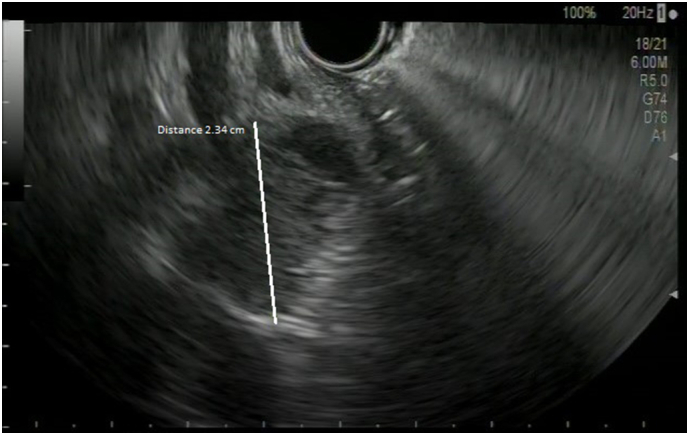

To avoid cholangitis, the patient rapidly underwent an endoscopic retrograde cholangiopancreatography (ERCP) with drainage of the lower CBD by a plastic stent. An endoscopic ultrasound (EUS) was performed at the same time, showing a nodule of the lower CBD infiltrating the head of pancreas and a biopsy of it was made (Fig. 2).

The latter showed a well-differentiated adenocarcinoma. We completed the pre-operative staging with a hepatic magnetic resonance that showed also a suspected malignancy of gallbladder with invasion of cystic duct and CBD (Fig. 3).